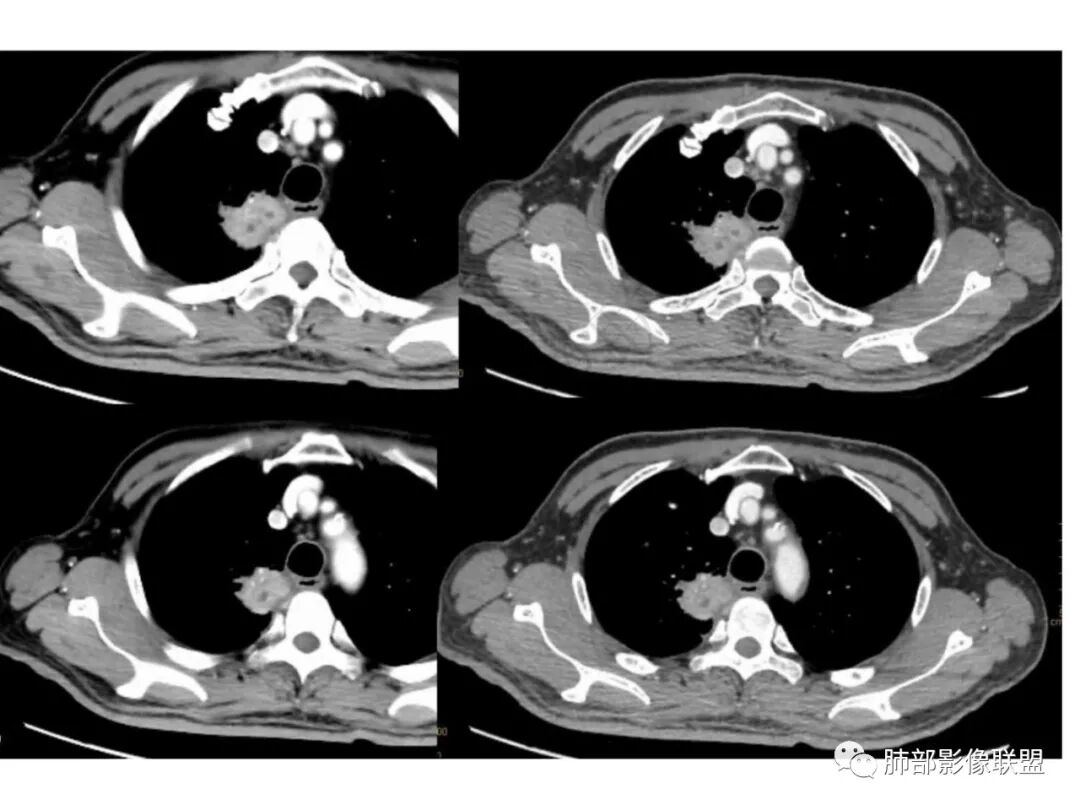

右上叶尖段带状实变影

外围大、内带小,宽基底与胸膜相连,附近卫星灶

支气管进入病灶内,广泛胸膜增厚

支气管粘液栓

血管走形自然

实变区强化较均匀,明显强化

边缘平直为主

支气管堵了,但是远端粘液栓:是粘液栓堵塞?还是狭窄或堵塞后继发粘液栓?

病灶是支气管腔内堵塞导致远端实变、不张?还是外围病灶融合、实变影响近端支气管?

整体考虑肿块应该不支持,因为支气管、血管走形还算自然,只是收缩在一起,如果肿块走形不会这么自然,会推移、变形,侵犯

现有的图显示近端支气管还是连续的,只是远端扩张,腔内粘液栓,其实还应当看重建的支气管连续的图,与近端含气部分的连续